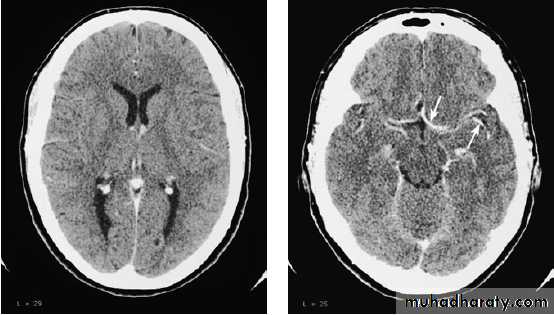

NEUROIMAGINGX-rays (plain X-rays, computed tomography (CT), myelography and angiography), magnetic resonance (MR imaging-MRI, or MR angiography-MRA), ultrasound (Doppler imaging of blood vessels), and radioisotopes (single photon emission computed tomography-SPECT, and positron emission tomography-PET).

A- CT scan